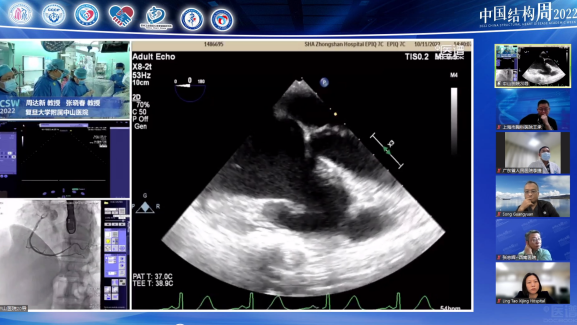

空军军医大学西京医院陶凌教授团队(术者:李飞教授)带来一例感染性心内膜炎重度AS患者。

针对本例患者,术者团队介绍了特殊情况,食道超声检查示无冠窦窦壁有囊性结构,考虑存在感染,血流通过无冠窦窦壁喷射到囊腔里面,随后询问病史患者自述有泌尿系感染1月余,故考虑合并感染性心内膜炎,囊性结构是陈旧性赘生物。有专家认为患者有脑梗死病史2月余,系囊性赘生物脱落所致。

与会专家针对食道超声发现的囊性结构展开激烈探讨,对于泌尿系感染和脑梗死的病因认为是赘生物脱落所致,在此情况下,建议该患者不太适合TAVR手术。李飞教授同意现场探讨内容,下一步策略计划再次评估CTA,局部采血后血培养,核磁明确,考虑到患者心衰严重,首先保守治疗后,选择SAVR(外科主动脉瓣置换术)还是抗炎后TAVR具体情况深入分析后在做抉择。但有专家更倾向于外科开胸换瓣,可以进一步分析病理。